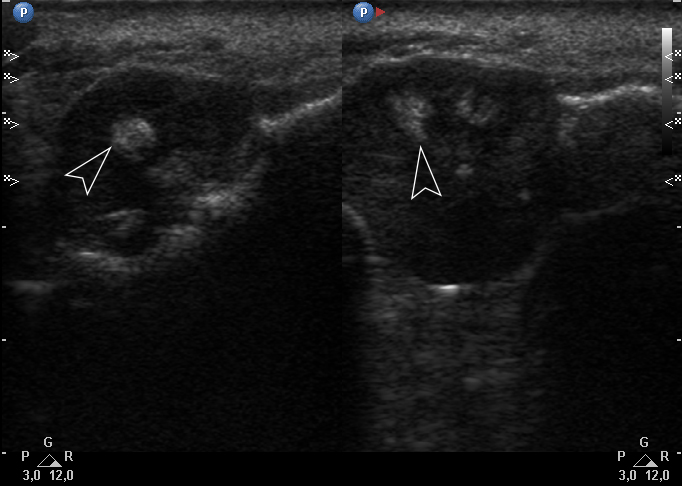

Gray-scale USG (Fig 4) revealed a unilocular, well-defined lesion with heterogeneous echogenicity. The lesion was measured 2.08 × 2.2 cm and located in a saddle-shaped position on the edentulous area of the anterior part of alveolar ridge of the mandible. The presence of multiple echoic areas and acoustic enhancement behind the neoplasm is noted.

FIGURE 4. Gray-scale ultrasound shows a unilocular, well-defined lesion with heterogeneous echogenicity. The lesion is measured 2.08 × 2.2 cm and indicated by “+” and “×” calipers. The lesion is located in a saddle-shaped position on the edentulous area of the anterior part of alveolar ridge of the mandible. Echoic area of bone formation is indicated by arrowhead. The area of the mandible on which the mass is located is indicated by an arrow and has a hyperechoic appearance. Acoustic enhancement is marked with an asterisk.

Color Doppler USG (Fig 5) showed prominent intralesional vascularity. Figure 6 demonstrates gray-scale USG of the lesion from two different angles, which allows for better visualization of echogenic areas (i.e., areas of ossification) within the lesion. It was not possible to adequately determine the area of the “stem” of the lesion.

FIGURE 6. Gray-scale sonograms of the lesion from two different angles (A, B). Sonograms show a hypoechoic lesion with multiple echoic areas (i.e., areas of bone formation). It is easy to distinguish areas of ossification (arrowheads) in the thickness of the lesion due to their echoic look. These two images demonstrate that gray-scale ultrasound is highly sensitive for detecting areas of ossification within a neoplasm such as PGCG.